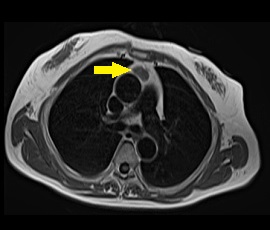

[気管支原性嚢胞] 手術:胸腔鏡下縦隔腫瘍手術

MRI画像